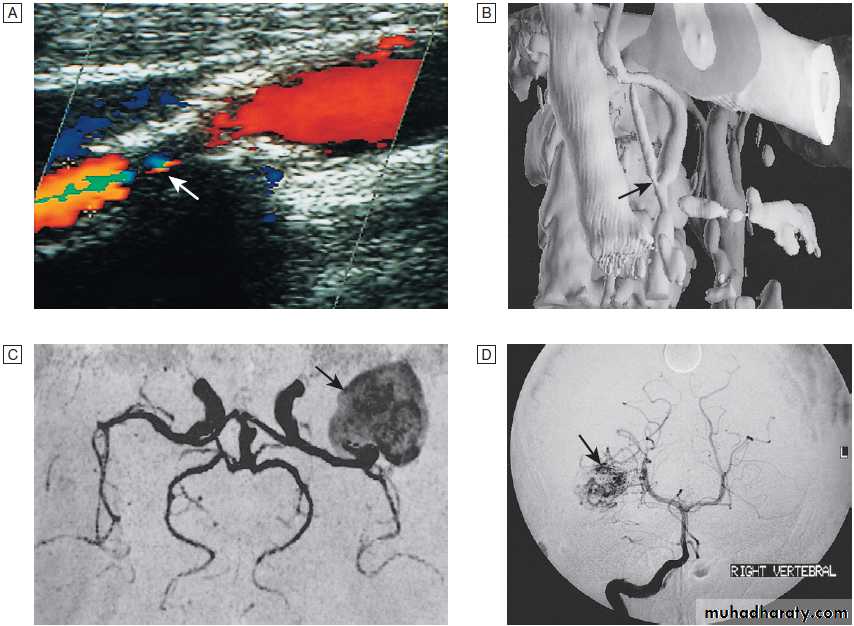

Fig. Different techniques of imaging blood vessels.

A Doppler scan showing 80% stenosis of the internal carotid artery (arrow).B Three-dimensional reconstruction of CT angiogram showing stenosis at the carotid bifurcation (arrow).

C MR angiogram showing giant aneurysm at

the middle cerebral artery bifurcation (arrow).

D Intra-arterial angiography showing arteriovenous malformation (arrow).